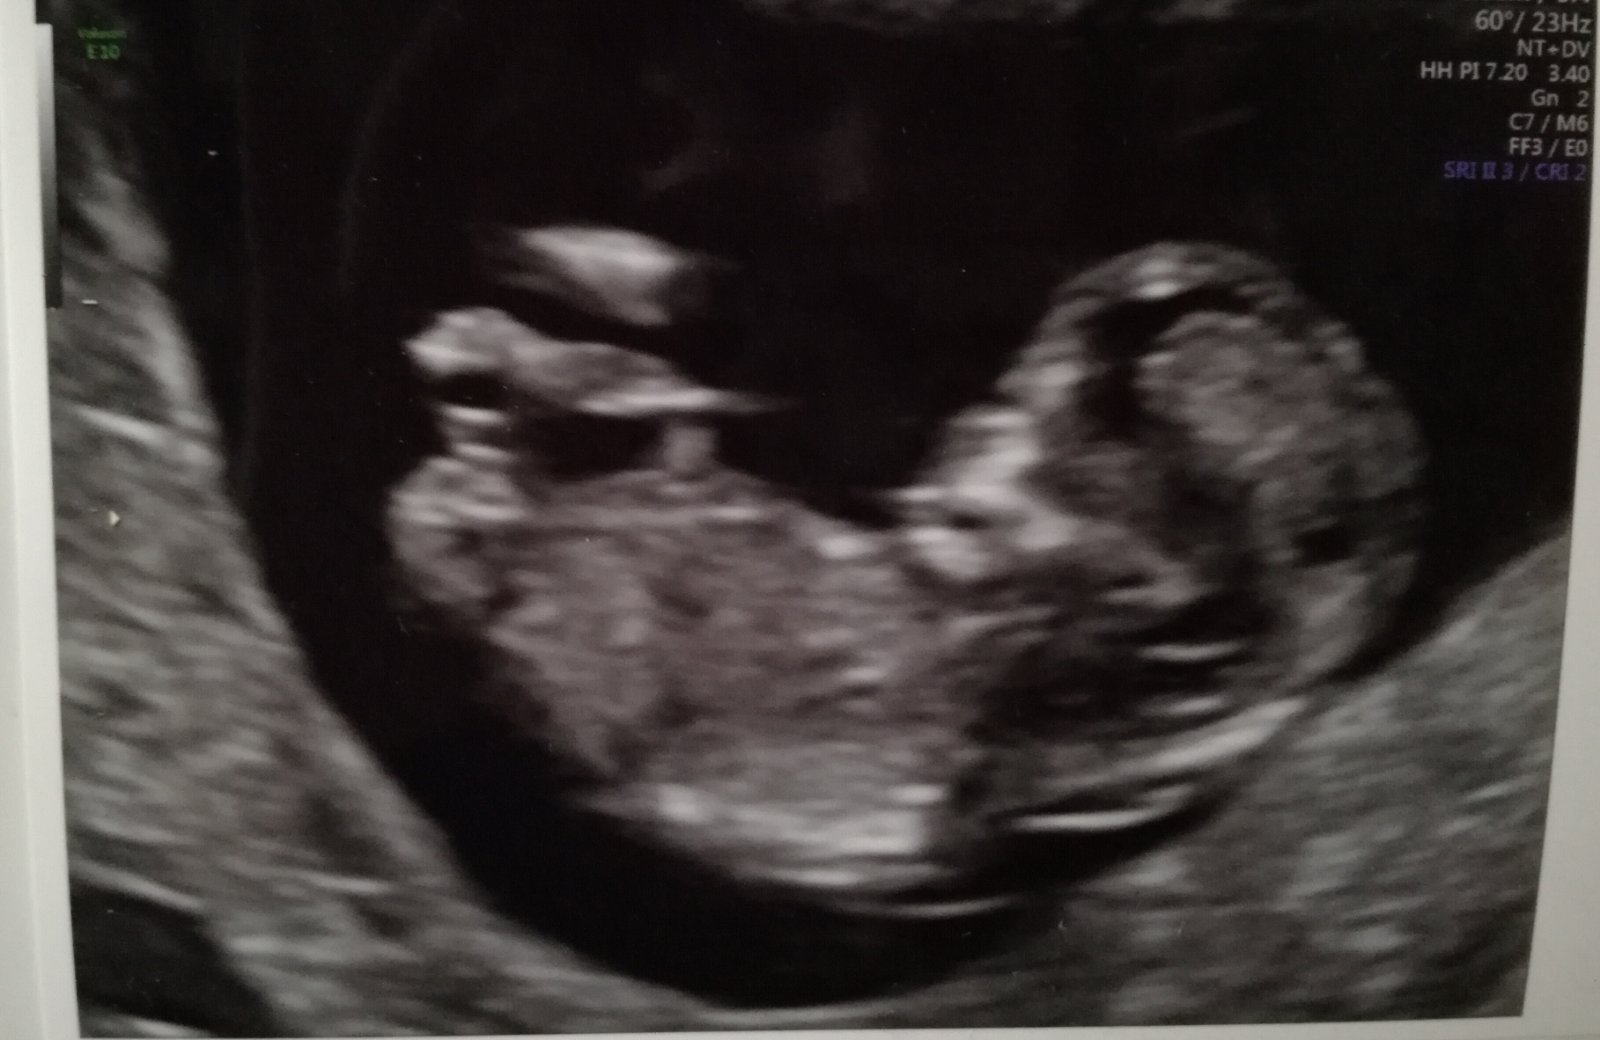

Ahoj holky. Já se zase po delší odmlce hlásím. U nás proběhla 4.4 první genetika a vše na jedničku.🤗🙏Nevolnosti už ustoupily a já se na začátku 2.trimestru cítím jako znovuzrozená.☺Pohlaví zůstává překvapením. 😊